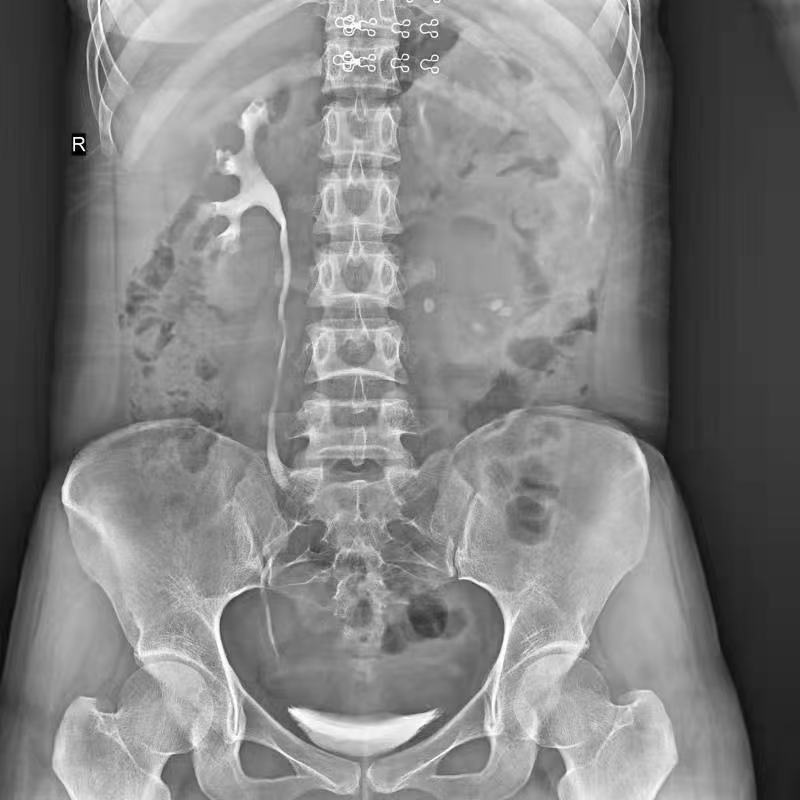

●呈現全下肢或全脊柱圖像

●在脊柱及下肢畸形矯正手術(shù)治療中,為術(shù)前方案制定和術(shù)后復查提供精準測量

●有效解決傳統X光片不能一次成像問(wèn)題,為患者提供更加優(yōu)質(zhì)的醫療服務(wù)